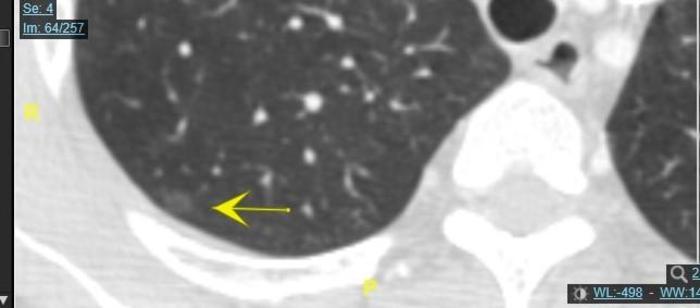

二、病例2.

这个磨玻璃结节6毫米,中心一个小空腔,总体磨玻璃结节影子比较淡。

病理为不典型腺瘤样增生,是原位癌前的阶段。一般不典型腺瘤样增生内部是没有小空泡的。有小空泡的起码是原位癌。不典型腺瘤样增生往往要缓慢增大,发展至原位癌阶段。